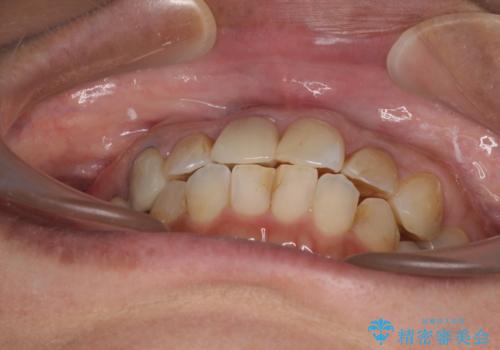

- 上下前歯のデコボコを気にして来院された患者様です。

歯列としては、ワイヤー装置でもインビザラインでも、どちらでも対応可能でしたが、処置されている歯が多く、ワイヤー装置を装着するためには処置歯のやり直しが必要な状態でした。

インビザラインでもアタッチメントを装着できないという同様のデメリットがありますが、比較的矯正治療を行いやすい歯列であったので、インビザラインによる矯正治療を行うこととしました。